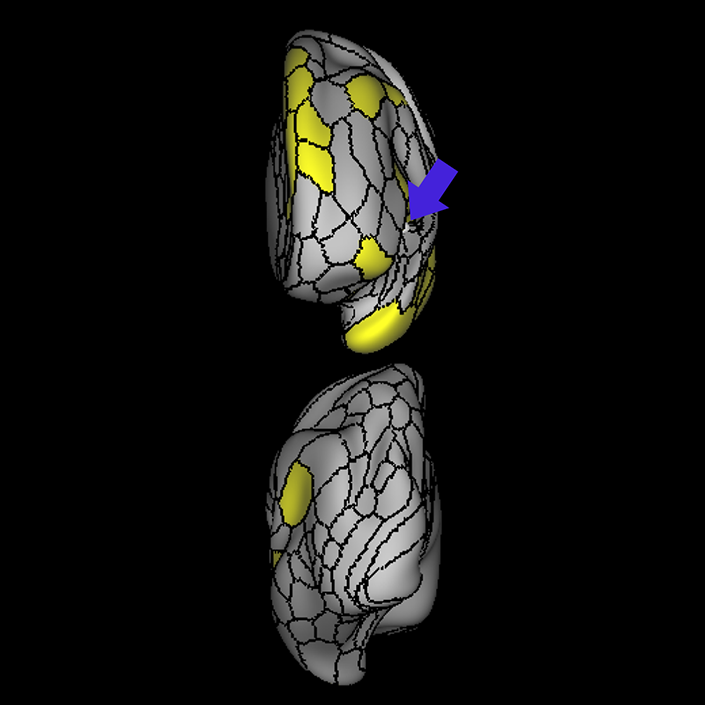

ᐅ SummaryArea 45: part of the inferior frontal gyrus of the lateral frontal lobe. In addition to its known association with Broca's area, is sometimes represented as part of Broca's complex ᐅ Where is it?Area 45 is the lateral surface of pars triangularis of the IFG. ᐅ What are its borders?Area 45 borders area 47L anteriorly and area 44 posteriorly. Its superior edge borders area p47r, IFSa, and IFSp. Its opercular surface is conveniently named FOP5 ᐅ What are its functional connections?Area 45 demonstrates functional connectivity to areas SFL, IFSp, 44, a47r, 47s, 47L, 9a, 9p, 9m, 8AV, and 8BL in the dorsolateral frontal lobe, area 8BM in the medial frontal lobe, area 55b in the premotor areas, areas FOP5, and PSL in the insula-opercular region, areas TGd, TGv, TE1a, STSva, STSdp and STSvp in the temporal lobe, area PGi in the inferior parietal lobe, and area 31pd in the medial parietal lobe. ᐅ What are its white matter connections?Area 45 is structurally connected to the arcuate/SLF and IFOF. However, arcuate/SLF connections are not consistent across individuals. Connections with the arcuate/SLF project posteriorly and wrap around the Sylvian fissure to the middle temporal gyrus to end at TE1p. There are also projections from the arcuate/SLF before it terminates to parcellations A4 and PBelt. IFOF connections travel from 45 through the extreme/external capsule and continue posteriorly through the temporal lobe to end at occipital lobe parcellations V1, V2, V3 and V4. Local short association bundles connect with 44 and FOP4. ᐅ What is known about its function?Area 45, in addition to its known association with Broca's area, is sometimes represented as part of "Broca's complex", including Brodmann Areas 45, 46, 47 and the mesial supplementary motor area of 6, which contribute to a frontal-subcortical circuit. |

A: lateral-medial

B: anterior-posterior

C: superior-inferior

DTI image |